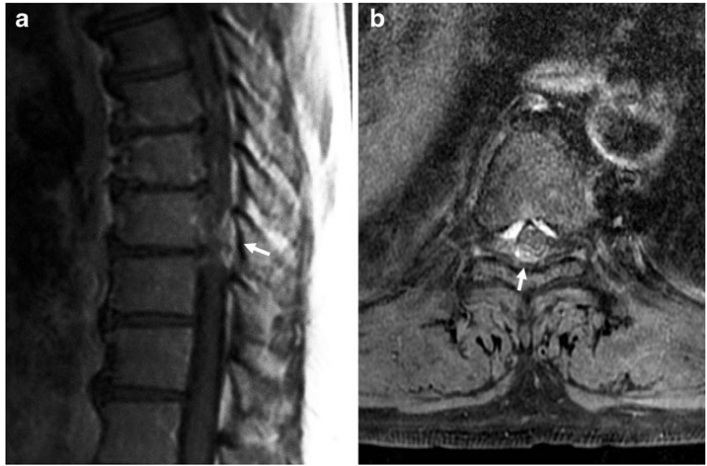

适应症:侧方型软性TDH或移位到硬膜囊侧方或背侧的游离型TDH该病案报道了一例极为罕见的T9-10椎间盘脱出后移至硬膜后外侧,行T9-10右侧椎板切除术。术者行显微镜手术而非内镜手术,但现有内镜微创技术可以完成该操作。

术前胸椎MR,T1加权成像(a)和轴位T1加权成像加脂肪抑制(b)显示T9-10水平有一个外周不均匀强化的硬膜外后侧肿块,压迫脊髓(箭头)。

术中探查为椎间盘髓核在硬膜背侧需要注意的是与硬膜外脓肿、硬膜外血肿、滑膜囊肿和硬膜外肿瘤的鉴别诊断,因为胸椎间盘脱出移位至背外侧是极其罕见的,往往需要行增强MR:1.神经系统症状为突发;2.硬膜外血肿:患者实验室凝血功能往往存在异常,但自发性血肿凝血功能可能正常,但早期血肿通常不会呈现增强信号,因为与血肿相关的边缘强化信号改变通常可见于其溶解状态;3.肿瘤或滑膜囊肿:一般来说,肿瘤或滑膜囊肿引起的神经系统并发症是逐渐发生的,且往往有相应病史。